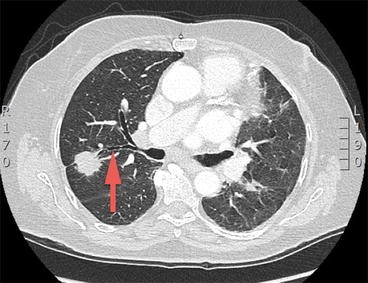

An 81-year-old lady with bilateral lung nodules. Axial computerized tomography scan shows a positive bronchus sign [red arrow right upper lobe posterior segment (RB2)] related to a mass in her right upper lobe

Surprisingly, the diagnostic yield for peripheral lesions reported in literature, both for the VB and ENB, is not significantly different [20, 21, 22, 38, 39, 40]. This may be due to lack of clear definition of the peripheral lesion. Pulmonary nodules are defined as 3 cm or less in size and surrounded by lung parenchyma [5, 47]; however, the definition of peripheral lesion lacks clarity in terms of location from the pleura and whether the lesion is endobronchially at the distal end of the tapering bronchus or completely in the lung parenchyma. The adjacent structures to the lesion or the distance to the pleura may alter the diagnostic yield or complication rate of the procedure. There is a need to clarify and define the peripheral lung lesion due to rapid advancements and comparison of different technologies with variable results [42].